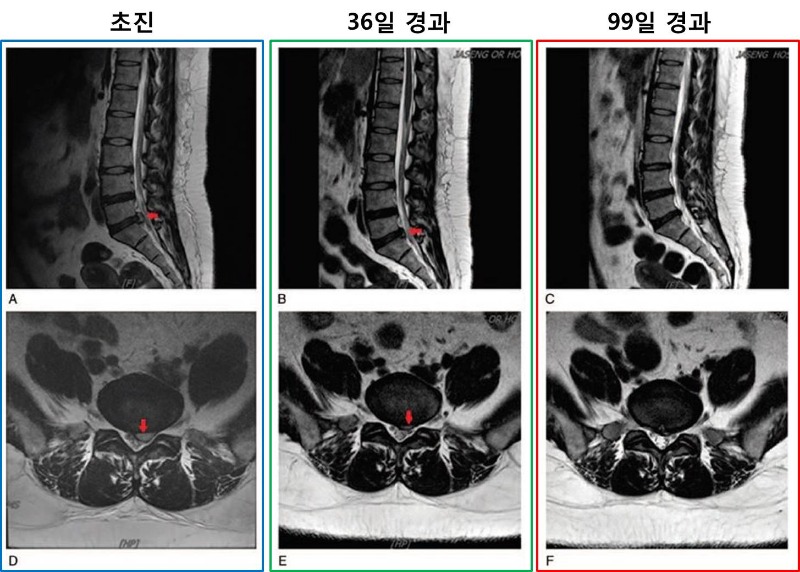

그 결과 한∙양방 비수술 통합치료를 실시한 지 36일이 지난 1차 평가시점에서 영상의학적으로 유의미한 디스크 낭종의 흡수가 확인됐으며 99일인 2차 평가에서는 디스크 낭종이 완전히 흡수된 것을 볼 수 있었다.

환자의 요통과 하지방사통 정도는 초진 당시 NRS가 8점 수준이었지만 치료 한 달 후에는 1점 수준으로 떨어졌고, 3개월 이후에는 0점 수준까지 감소해 통증이 완전히 없는 상태가 됐다.

의료진은 한∙양방 비수술 통합치료의 효과를 알아보기 위해 치료 시작 후 1∙3개월되는 시점에 요추 MRI를 통해 디스크 낭종 상태를 실폈고 환자 입원 기간 동안 주 1회, 치료 시작 후 2∙3∙6개월이 지난 시점에 NRS, 기능장애지수(Oswestry Disability Index, ODI), 삶의 질 평가(EQ-5D), 공포-회피 반응 설문지(Fear-Avoidance Beliefs Questionnaire, FABQ)로 환자의 상태를 다각도로 평가했다.